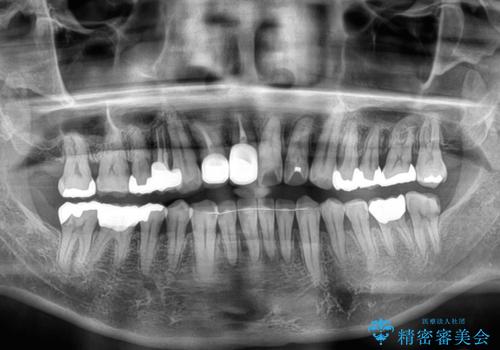

- 隠れるほどに内側に転位しいてる前歯を気にして来院された患者様です。

仕事柄海外出張が多いとのことで、インビザラインにて矯正治療を行うこととしました。

矯正治療後は、前歯や下顎の奥歯など、むし歯治療途中の歯をオールセラミッククラウンにて補綴治療を行うこととしました。

治療途中で海外に長期滞在することとなり、5年近く帰国することができなかったため、治療期間は非常に長いものとなりました。

内側に転位していた前歯は、矯正治療では治しきることができませんでしたが、幸いにもオールセラミッククラウンに置き換える予定であったため、希望通りの仕上がりとなりました。